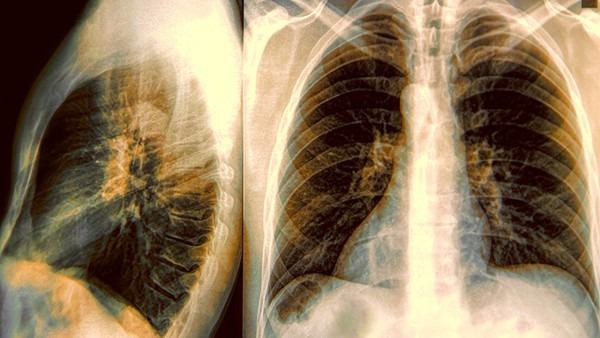

要及早发现无症状性支气管结核,关键在于定期进行体检。尤其是有一定风险的人群,应该定期接受胸部X射线检查或结核杆菌检测等相关检查。这些人群包括与结核患者长期接触的亲属、医务人员、糖尿病、艾滋病等免疫系统较差的患者,以及长期使用免疫抑制剂的人群等。